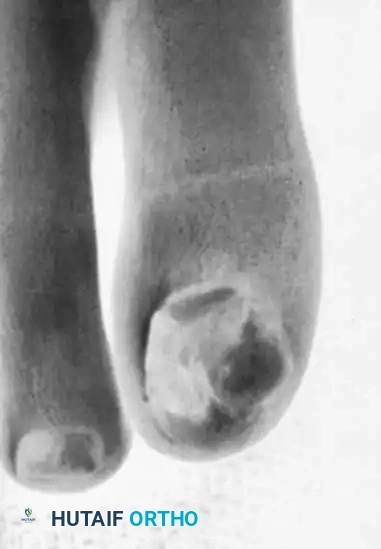

Fig. 84-24B: The clinical appearance of the digits immediately after mechanical nail reduction, alleviating the deforming forces.

Clinical Management and Nail Reduction

Routine conservative management requires specialized instrumentation. Having a small double-action rongeur and a heavy-duty nail splitter-cutter in the outpatient clinic is highly recommended. These hypertrophic nails can be reduced quickly and safely with these instruments, immediately relieving the mechanical pressure on the nail bed.